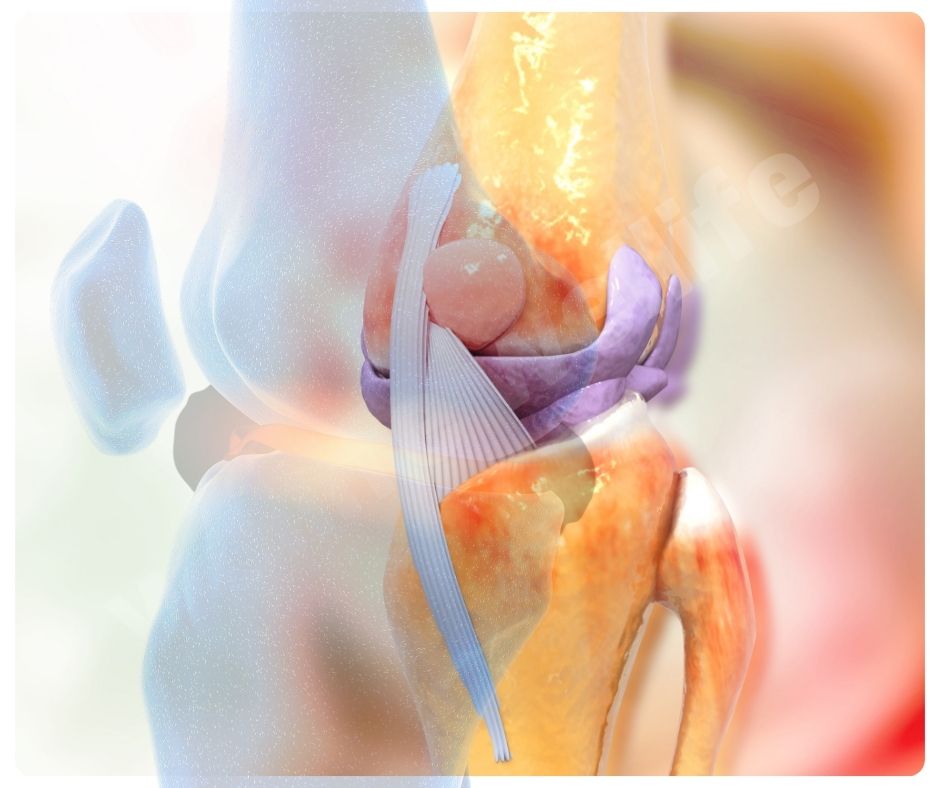

콘드로이친은 연골의 중요한 구성 성분으로, 관절을 보호하고 부드럽게 움직이게 도와주는 역할을 해요. 주로 동물의 연골에서 추출되며, 관절염 환자들이 많이 찾는 보충제랍니다.

콘드로이친 효능 중 가장 대표적인 것은 골관절염(Osteoarthritis) 완화입니다. 골관절염은 연골이 닳아 없어지면서 통증과 강직을 유발하는 만성 질환인데요, 콘드로이친은 연골 손상을 줄이고 증상을 완화하는 데 효과적이에요.

- 연골 보호 및 재생: 콘드로이친은 연골의 구조를 유지하고, 손상된 연골의 재생을 돕는 효능이 있습니다.

- 통증 완화: 관절 통증을 줄이고, 관절의 기능을 개선하는 데 도움을 줍니다.